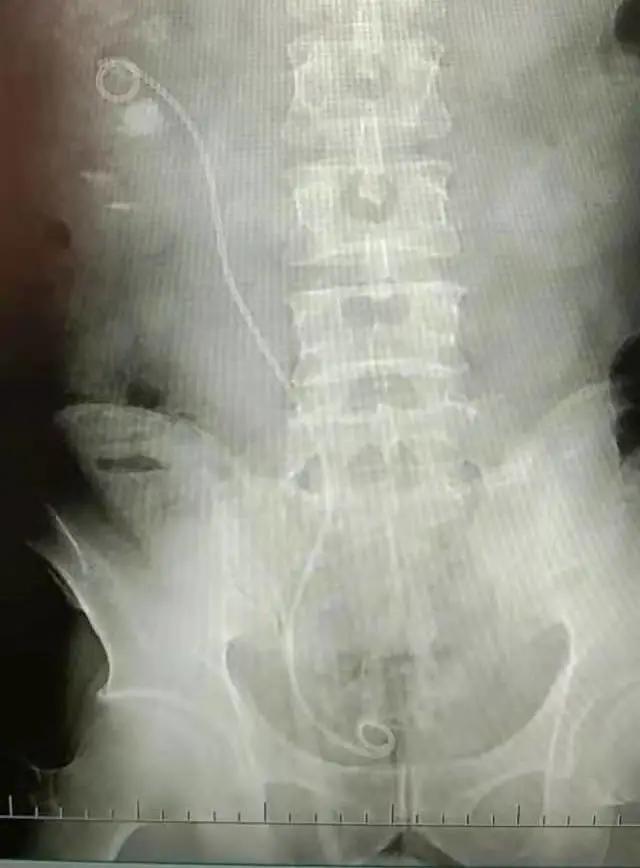

第一次术后X光片

第二次术后X光片